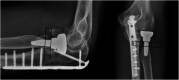

Figure 1.

Radiographs demonstrating the zones of radiographic changes used for this study in accordance with Popovic et al. along with incidence of periprosthetic lucency by zone at radiographic follow-up. Case 5 (Final AP and lateral images at 83 month follow-up). Lucent lines surrounding the stem in all zones with a loose stem at final follow up.